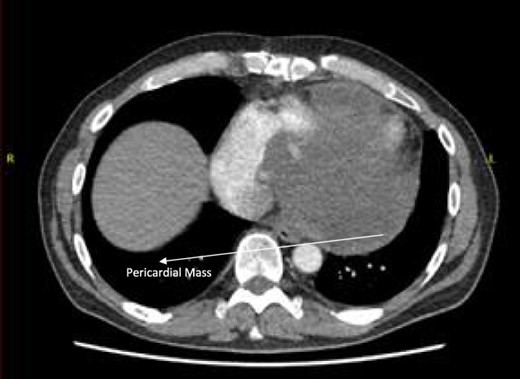

A 52-year-old gentleman was admitted to a district general hospital for shortness of breath causing type 1 respiratory failure with oxygen saturations of <90% despite high flow oxygen. His past medical history was unremarkable, and he was usually fit and well. A CT Pulmonary Angiogram (CTPA) was undertaken, which showed a heterogeneous oval-shaped lesion measuring 15 × 9 × 14 cm3 between the heart and the diaphragm, with a median attenuation of 35 HU and no enhancement during the arterial phase. Further solid lesions of 14 mm in the right lower lobe and 5 mm in the right upper lobe raised the suspicion of a primary cardiac sarcoma with pulmonary metastasis. This is shown in Fig. 1. Subsequent urgent CT staging (Fig. 2) was undertaken, which confirmed an indeterminate space occupying the inferior pericardial space, right atrial (RA) filling defect and anterior nodular pericardial thickening. No intra-abdominal or bone lesions were identified. An echocardiogram also confirmed these finding with the addition of no flow through the tricuspid valve (TV), as shown in Fig. 3.

CTPA showing oval-shaped heterogenous lesion as well as RA filling defect.